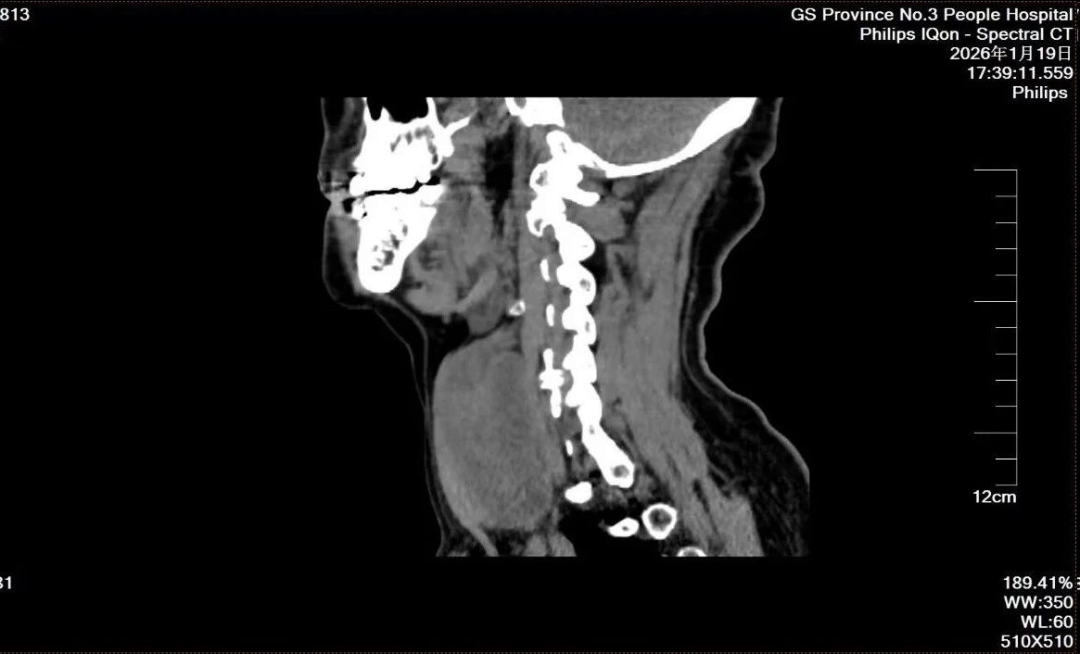

患者为60余岁老年女性,颈部肿物病史较长,曾在多家医疗机构就诊。随着病程进展,肿物持续增大,直径约7厘米,体积较大,局部解剖关系复杂,手术难度和风险明显增加。

同时,患者合并高血压并有既往脑梗死病史,属于多系统疾病叠加的高风险人群,对围术期评估、麻醉管理及手术安全提出了更高要求。